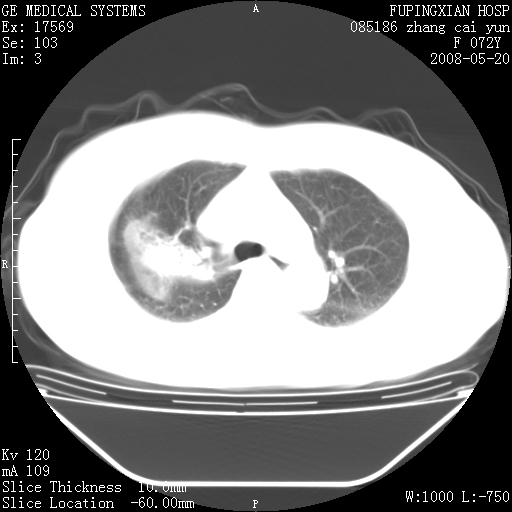

标题: CT13542:发热,咳嗽数日,经抗菌素治疗好转,请大家看排除 [打印本页]

标题: CT13542:发热,咳嗽数日,经抗菌素治疗好转,请大家看排除

右上叶支气管走行自然,未见明显管壁增厚等征像,另左主支气管起始部可见异常腔道向左侧延展左肺动脉干后方,与左下叶支气管相通,为左下叶支气管变异?

有节段性阻塞性肺炎与不张,近段支气管狭窄,周围散在肿大淋巴结影,以周围型肺癌可能性大,建议纤支镜检查。

右肺上叶实变影,内见支气管充气征,右上叶支气管通畅,肺门区未见软组织密度影,抗炎治疗有效,考虑炎症,建议继续抗炎治疗复查。

考虑为:右肺上叶感染性病变。建议:1)继续抗炎治疗后复查。2)必要时行纤支镜检查。

右上肺实变,间内有支气管充气征,考虑炎症,建议抗炎后复查